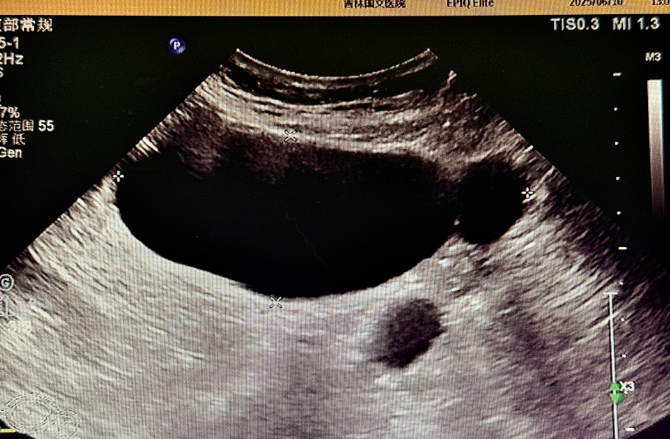

為精準(zhǔn)判斷病情,患者術(shù)前接受了多項(xiàng)影像學(xué)檢查:盆腔 MR 平掃顯示,腹腔內(nèi)存在囊性病灶,周?chē)橛泄軤钣跋?,為病變定位提供了重要線索,下腹部 CT 進(jìn)一步提示輸卵管擴(kuò)張,腹盆腔內(nèi)可見(jiàn)低密度病灶,與 MR 結(jié)果相互印證,超聲檢查發(fā)現(xiàn)附件區(qū)有管狀無(wú)回聲結(jié)構(gòu),經(jīng)超聲科與婦科專(zhuān)家聯(lián)合會(huì)診,綜合分析后診斷為輸卵管積水。多項(xiàng)檢查數(shù)據(jù)的交叉驗(yàn)證,如同為醫(yī)生裝上 “透視眼”,讓隱藏的病灶無(wú)所遁形,為后續(xù)手術(shù)方案的制定打下了堅(jiān)實(shí)基礎(chǔ)。